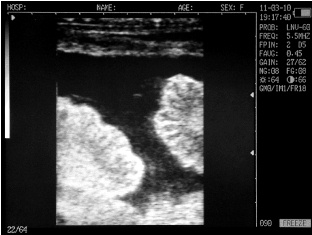

Ultrasound images of cows reproductive system, generated by a scanner Sonovet with rectal linear transducer.

Uterine horn heifers